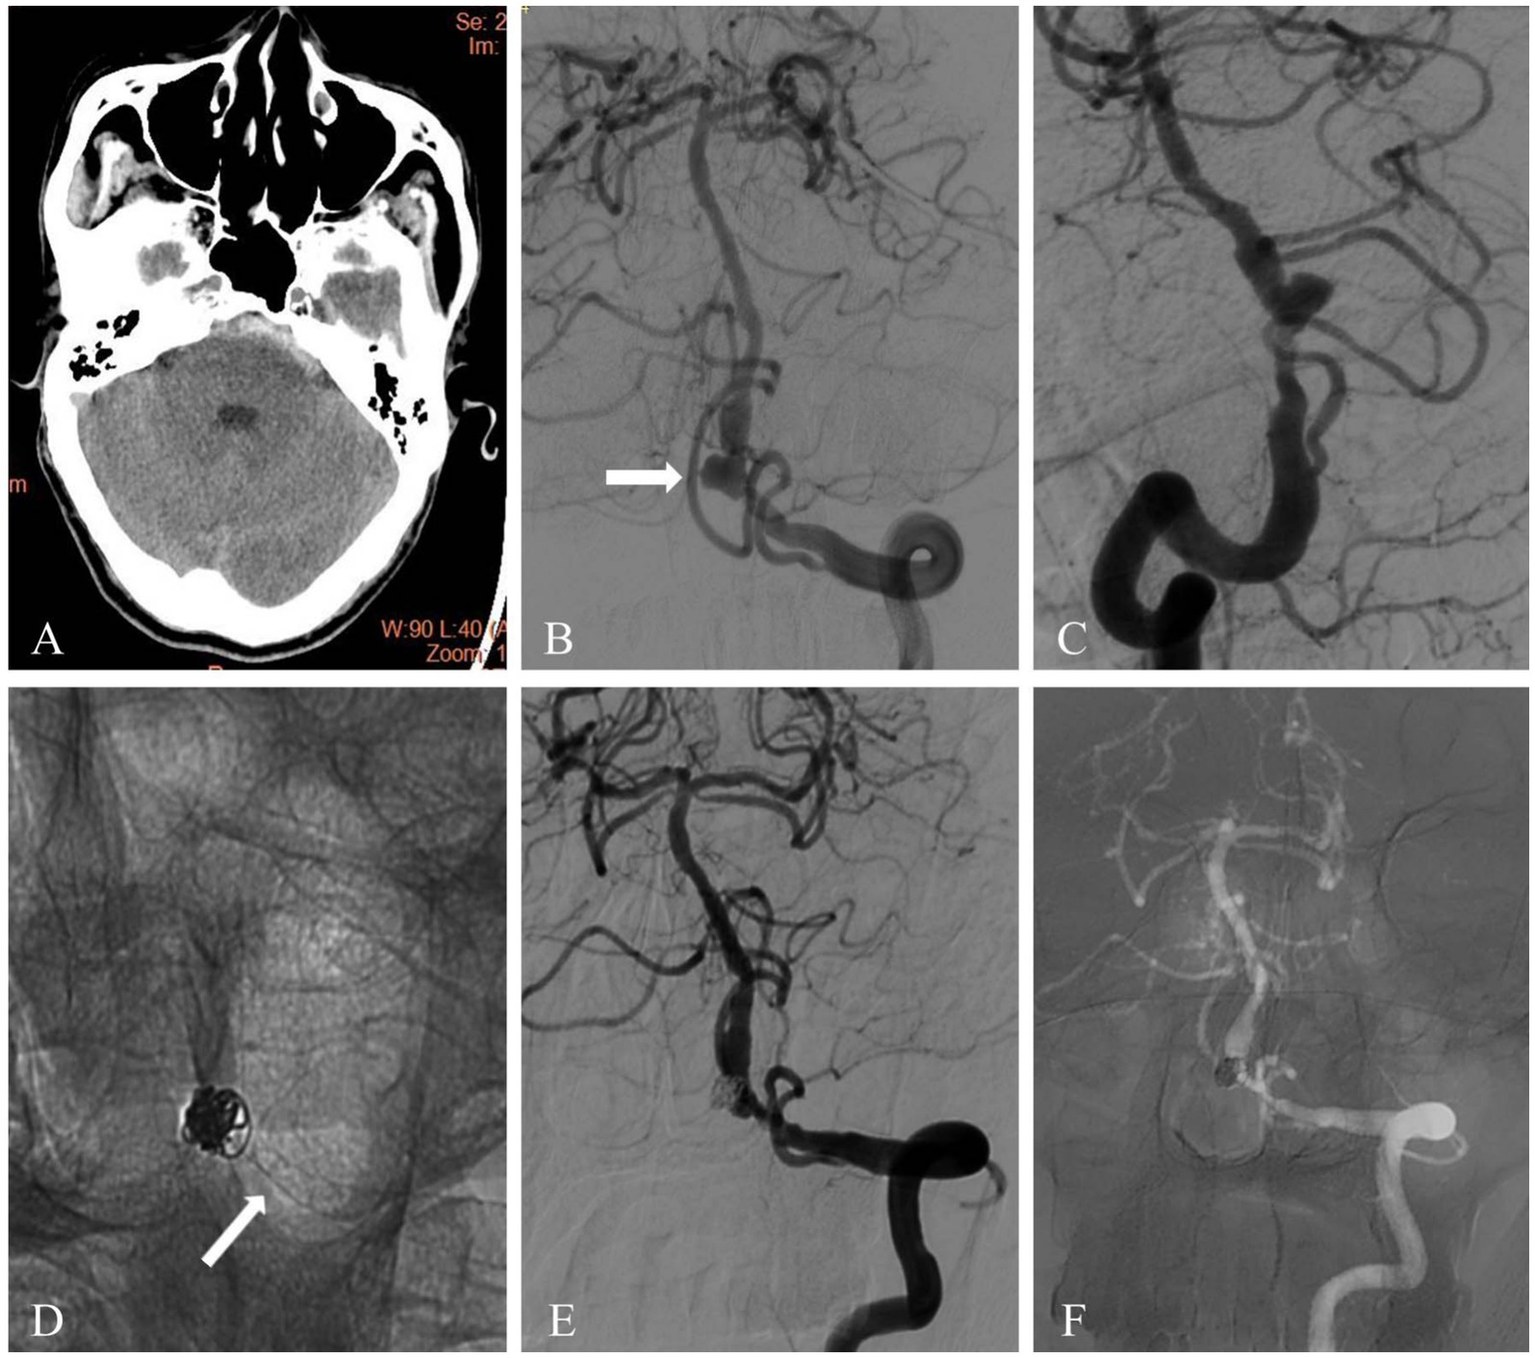

Figure 1

A ruptured blood blister aneurysm was treated with PED and adjunctive coiling. (A) Head computed tomography image of a 51-year-old patient showed acute subarachnoid hemorrhage. (B,C) Diagnostic cerebral angiography revealed a blood blister aneurysm located on the supraclinoid segment of the right internal carotid artery (white arrow). (D) The aneurysm was treated with PED and adjunctive coiling. Fluoroscopic image showed the flow diverter and coil mass (white arrow). (E) Immediate angiography after PED deployment showed complete occlusion (white arrow). (F) Follow-up angiography at 10 months showed complete occlusion of the aneurysm (white arrow).